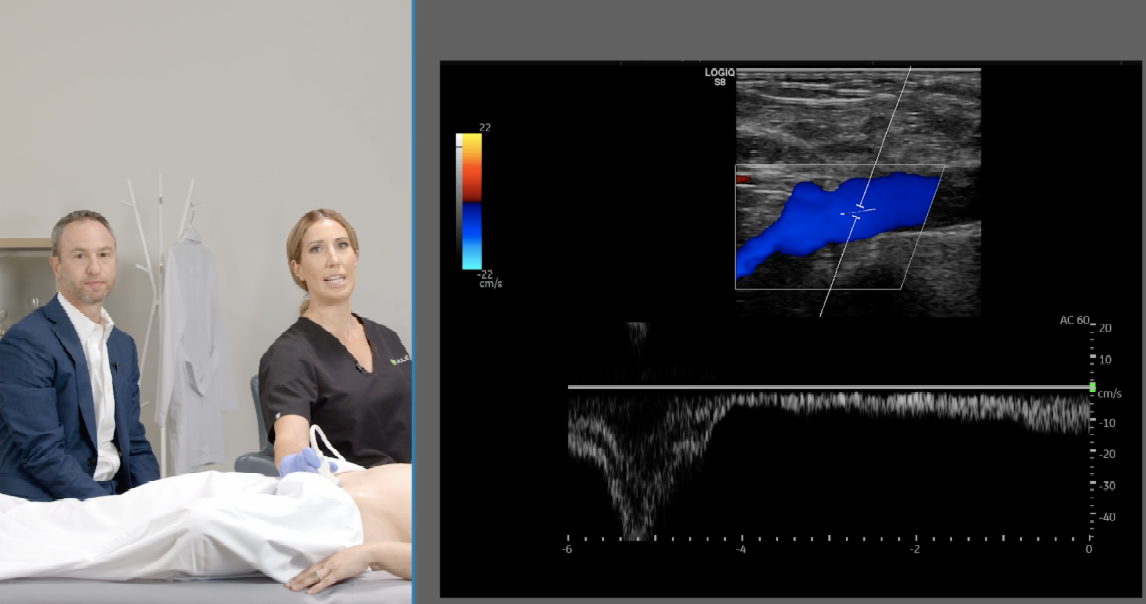

Teaching Tidbit: Right Iliac Vein Compression

An elderly woman presented to the vascular lab with curious symptoms.

Although she received prior venous treatment, her relief of symptoms were only temporary.

She returned with recurrent right leg pain and swelling identical to her initial visit.

Due to her clinical presentation and recurrent symptoms, a ultrasound of the outflow veins was ordered by the physician...